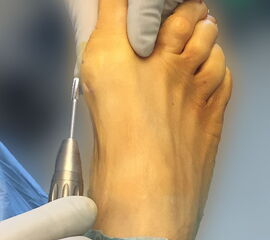

Das hier vorgestellte Konzept beruht auf den grundsätzlichen Überlegungen von Sharma, unter Anwendung der Prinzipien der minimalinvasiven Fußchirurgie. Die Korrektur der Adduktionsfehlstellung der Metatarsalia II bis IV erfolgt über eine modifizierte, lateralisierende, distale, minimalinvasive Metatarsale-Osteotomie (DMMO) (interner Link: OP Technik DMMO). Die Osteotomie der Metatarsalia II bis IV ohne Osteosynthese erlaubt eine limitierte Verlagerung der Metatarsaleköpfchen nach kranial, was ein etabliertes Verfahren zur Therapie einer Metatarsalgie darstellt 7. Eine zusätzliche, im Normalfall unerwünschte Lateralverschiebung der Metatarsaleköpfchen kann bei einem Pes adductus zur Korrektur genutzt werden. Verglichen zu offenen Therapieverfahren ermöglicht dieses Konzept die Korrektur der Adduktionsstellung der Metatarsalia II bis IV bei minimiertem Weichteiltrauma und verkürzter die OP-Dauer. Persönliche Erfahrungen mit dem Verfahren deuten darüber hinaus auf ein geringeres postoperatives Schmerzniveau, eine einfachere Mobilisierbarkeit und eine hohe kosmetische Zufriedenheit hin.

• Fuß ist auf der unteren Tischkante gelagert, so dass der Zugang von allen Seiten möglich ist (Abb. 3).

Zum Lesen der Bildbeschreibung und zur Vollansicht bitte die Bilder anklicken.